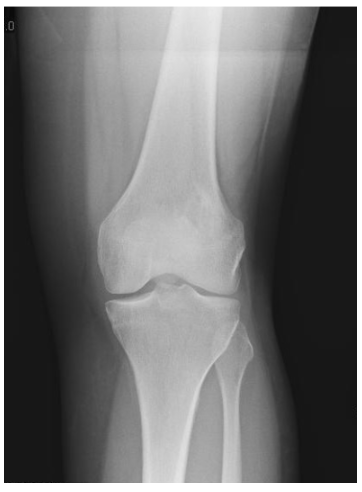

Intraosseous Osteosarcoma Xr

• • Most commonly occurs in long bones (femur, tibia, fibula, humerus, radius, ulna, etc.).

• • Tumors most commonly arise around the knee.

• • The work-up for Low-Grade Intraosseous Osteosarcoma often consists of a physical examination, X-ray, MRI, and CT scans. A chest CT is performed to evaluate whether the cancer has spread to the lungs. CT PET scans and other bone scans may also be performed to determine the local extent of cancer in the bone and whether the cancer has spread to other parts of the body. The diagnosis is often confirmed with a biopsy, which samples the tumor for further analysis.

Differential diagnoses include fibrous dysplasia, low-grade fibrosarcomas, parosteal osteosarcoma, or other benign lucent lesions such as osteoblastoma, chondroblastoma, giant cell tumor and non ossifying fibroma depending on location. Therefore, radiographic imaging is used to help form a diagnosis. These include X-Ray, MRI, CT and Bone Scans